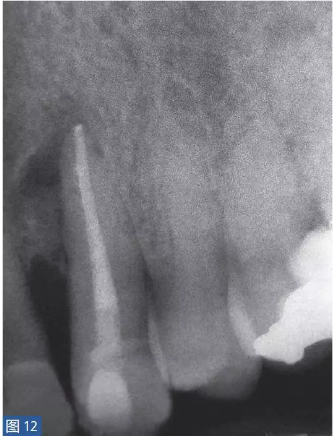

根尖周囊腫(圖12 和13)總是與無(wú)癥狀的根尖周炎相關(guān)。目前普遍認(rèn)為,通過(guò)上皮殘留細(xì)胞的炎性增殖形成了根尖周囊腫。在組織學(xué)上,它們分為袋囊腫(pocket cyst)和根尖周真性囊腫(periapical true cysts)。通常認(rèn)為,袋囊腫可以通過(guò)單純的根管治療而非手術(shù)方式,即通過(guò)細(xì)胞凋亡(apoptosis)和程序性細(xì)胞死亡(programmed cell death)達(dá)到愈合。這種方式在真性囊腫似乎不太可能實(shí)現(xiàn)。

圖12: 23 牙齒根尖周囊腫 。非手術(shù)治療,采取單純的根管治療后的X 線片檢查。因未愈合而決定采取手術(shù)治療。

圖13:手術(shù)性根管治療一年后的對(duì)照X 線片顯示根尖病灶已愈合。對(duì)搔刮出的組織進(jìn)行組織病理學(xué)檢查顯示為真性根尖周囊腫。